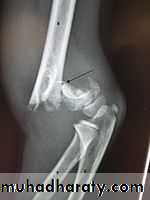

Intercondylar fracture of humerus:

Lateral condyle fracture of humerus:

Medial condyle fracture of humerus: